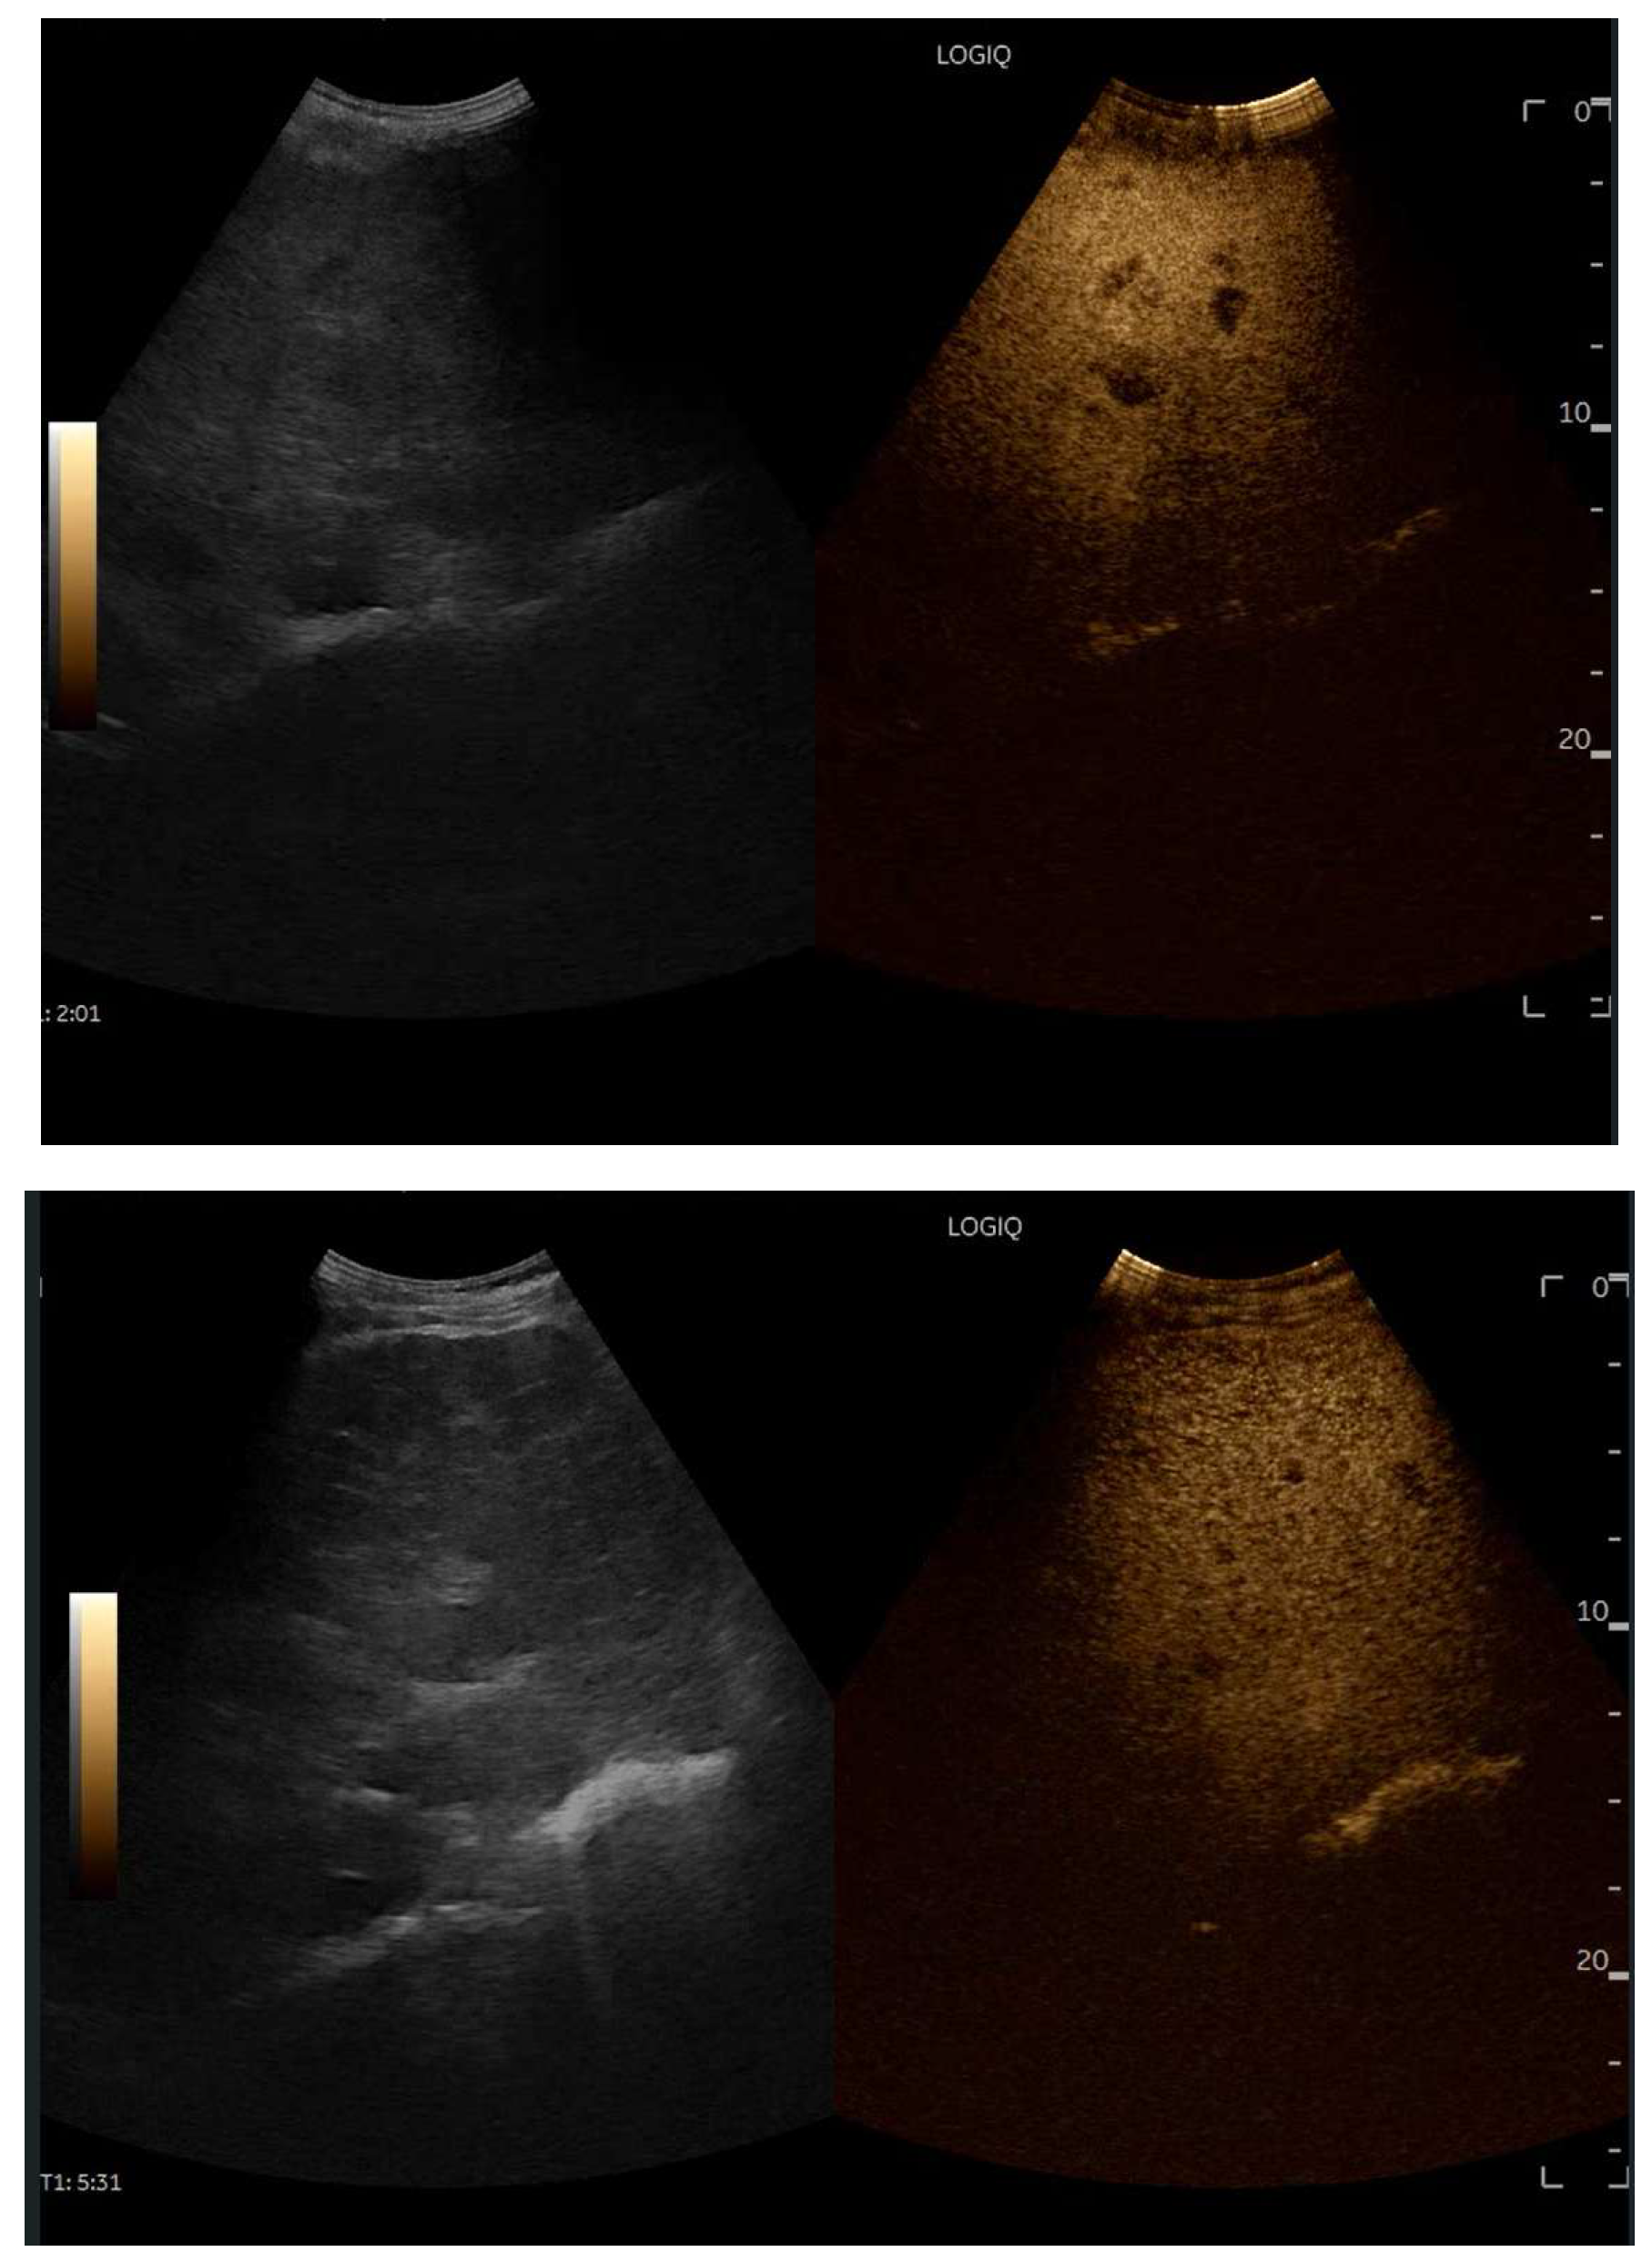

CEUS is valuable for characterizing the contrast enhancement patterns of liver nodules [68,69,70,71]. In Europe, the US contrast agent SonoVue® (sulfur hexafluoride; Bracco, Milan, Italy) is approved only for intravenous applications in patients over 18 years of age [72]. CEUS use in Fontan patients remains limited due to their frequent collateral circulation with right-to-left shunts, which is considered a contraindication in Europe but not in the United States. Beyond structural liver changes, CEUS reveals markedly heterogeneous hepatic enhancement with mosaic or reticular patterns, mainly due to slow and reduced enhancement near congested hepatic veins—one of the most common imaging features of FALD [54,73]. Anecdotal experience suggests that CEUS demonstrates heterogeneous and decreased liver enhancement in the portal venous phase, similar to cirrhosis of other etiologies (Figure 14, Figure 15). Abnormal enhancement is more prominent at the liver periphery than centrally, while the hypertrophic caudate lobe often shows more homogeneous enhancement. In patients with FALD, the altered hemodynamics resulting from chronic hepatic venous congestion and low cardiac output can significantly influence CEUS dynamics. Despite these circulatory changes, CEUS in FALD generally preserves the standard temporal enhancement pattern. The hepatic veins, although congested, do not typically show early enhancement, as microbubble distribution primarily reflects arterial input. The systemic hypokinetic circulation characteristic of FALD may lead to delayed arterial arrival times and a prolonged transit of contrast, especially in the background of the liver. Nonetheless, FNH-like nodules frequently exhibit intense and early arterial-phase hyperenhancement, suggesting preserved or increased arterial supply in these lesions. This contrast behavior is essential for lesion characterization.

Figure 14.

Contrast-enhanced ultrasound (CEUS) in the late phase shows the appearance of hypo-vascular areas due to varying degrees of congestion and hepatic alteration. These areas may mimic malignant nodular lesions with early washout.

Figure 15.

CEUS exam showing late heterogeneous enhancement in the arterial phase with evidence of hypo-enhanced areas, thus mimicking a malignant wash-out.

CEUS plays a crucial role in evaluating hepatic nodules in FALD and Figure 16 (Figure 17). In non-cardiac cirrhosis, contrast washout in the late phase is highly indicative of HCC. However, in FALD and other congestive hepatopathies like Budd–Chiari syndrome, FNH-like nodules can also exhibit delayed washout, leading to false positives if the LI-RADS system is strictly applied [74]. An FNH-like lesion is a benign hyper-vascular regenerative nodule that mimics focal nodular hyperplasia on imaging but arises secondary to chronic hepatic venous congestion and altered perfusion, typically occurring in FALD or other forms of congestive hepatopathy. Washout in the portal venous phase, in contrast, is uncommon in FNH-like nodules and more specific for HCC [69]. Despite limitations, ancillary LI-RADS criteria and portal venous phase washout remain useful for identifying potentially malignant lesions [75,76].